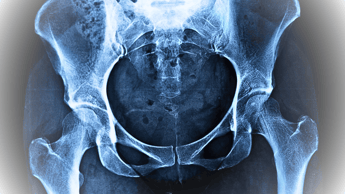

Introducción a las Fracturas de Cadera

Las fracturas de cadera son particularmente preocupantes, especialmente en personas mayores, ya que pueden llevar a complicaciones severas si no se tratan adecuadamente. Estas fracturas generalmente ocurren en dos áreas del fémur: el cuello del fémur y la región intertrocantérica. La intervención temprana es esencial para minimizar el tiempo de recuperación y evitar complicaciones como trombosis venosa profunda o infecciones.

Identificación de una Fractura de Cadera

Para identificar o sospechar una fractura de cadera solo con observar la lesión, existen dos elementos clave:

Acortamiento de la extremidad afectada: La pierna del lado afectado puede parecer más corta que la otra.

Rotación externa: La pierna lesionada suele girarse hacia afuera.

Además de estos signos visibles, otros síntomas incluyen:

Dolor intenso en la zona de la cadera o ingle.

Incapacidad para caminar o levantarse después de una caída.

Hematomas e hinchazón alrededor de la cadera.